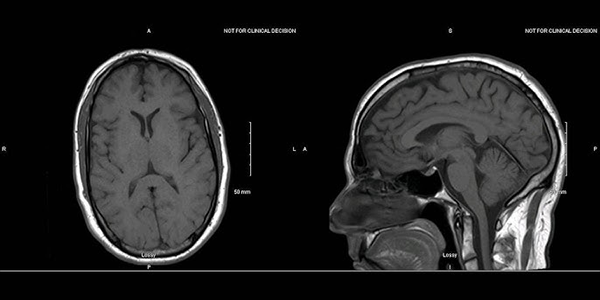

Kontrastsız MR, Manyetik Rezonans Görüntüleme (MR) teknolojisi kullanılarak vücudun iç yapılarının detaylı görüntülerini elde etmek için kullanılan bir yöntemdir. Bu yöntemde, damar yoluyla kontrast madde enjekte edilmez. Kontrastsız MR, beyin, omurilik, eklemler, iç organlar ve kaslar gibi birçok farklı bölgenin incelenmesinde kullanılabilir.

• Beyin MR: Beyin tümörleri, inme, MS ve diğer beyin hastalıklarının teşhisinde kontrastsız beyin MR kullanılabilir.